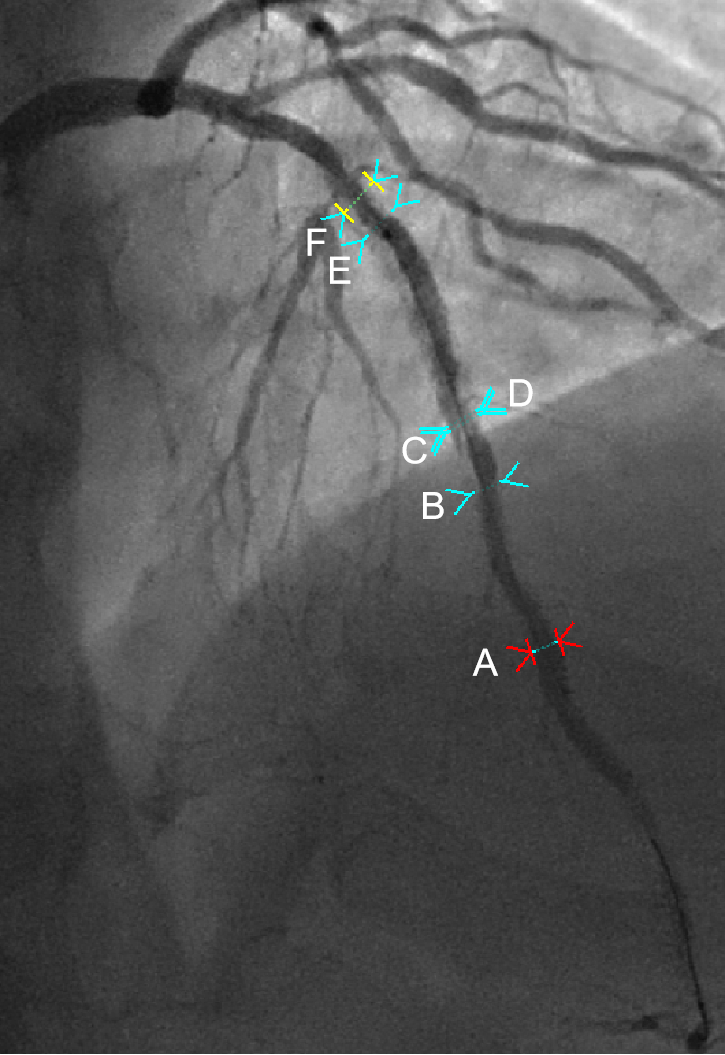

图注:

图中A-B段:15.1mm:2.5*16mm支架,新生内膜增生

图中B-C段:无支架段,支架边缘夹层

图中D-F段:27.2mm:2.75*28mm支架

图中C-F段:28.1mm:3.0*29mm支架, 2008年ISR植入

图中E以近:3.0*20mm支架

因此,图中D-E为双层支架,E-F为三层支架。